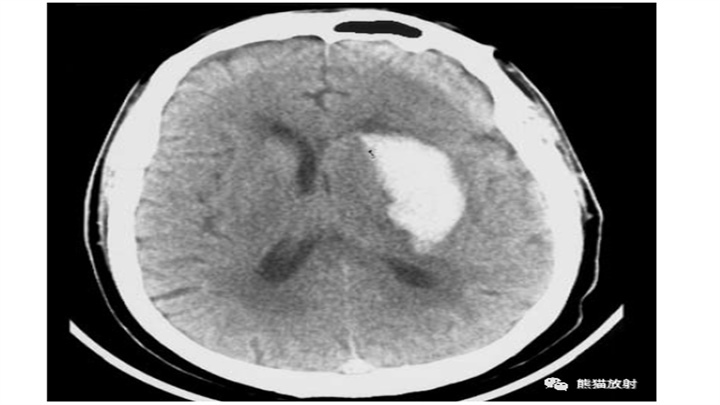

大量脑出血,累及左丘脑和基底节。明显的占位效应(中线结构向对侧明显移位)和脑室积血(同侧脑室变扁,右侧枕角积血)。然而,像往常一样,腹周水肿的数量仅限于周围边界。患者在数小时后死亡。